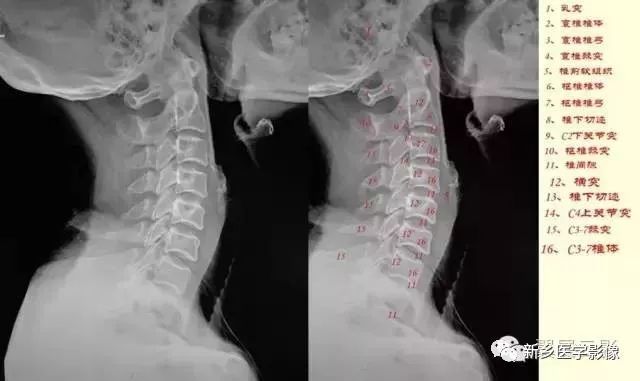

颈椎侧位

颈椎侧位片可以观察椎体前缘连线形成的弧度及生理曲度的变化,在正常情况下稍向前凸。观察椎体的整体形状,对比每个椎体的变化。观察每个椎体与上下椎体之间的关系。寻找椎体后缘可疑的变化。如椎体脱位。观察椎间隙及相邻椎体的边缘。观察有无A 椎间隙变窄;B 前缘唇样变;C 后缘唇样变;D 强直性脊柱炎所致的椎体融合。

①、曲度的改变:颈椎变直、生理前突消失或反弯曲,除病人的投照位置、投照角度等技术因素之外,可能会有几种原因:

第三、由于颈椎间盘变性部位不同,程度不一,也可发生曲度的改变及局部旋转或偏歪现象而表现为局部棘突偏歪;关节突、椎根切迹及椎体后缘呈双影现象。在侧位片,以下三种情况有临床意义:

a:一个或两个颈椎椎间小关节突呈有双影,称为双凸现象;椎根切迹呈有双影,称为双凹现象;椎体后缘呈有双影,称为双边现象,而上下颈椎却显影正常,表示其颈椎有旋转现象。

b:上部颈椎显影正常,而下部颈椎呈现双凸、双边、双凹现象;或下部正常而上部有类似的变化,表示其交界部有旋转现象。

c:颈椎的一个或两个脊椎显影正常,而其部分有双凸、双凹、双边现象,表示显影正常的颈椎有旋转现象,如全部颈脊椎的后部呈现双凸、双凹、双边现象,则为投照不当的原因,无临床意义。